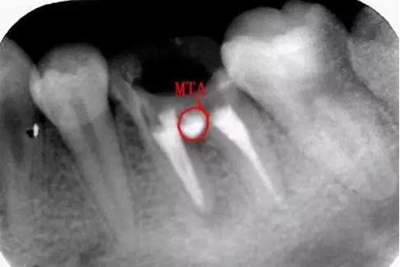

沖洗后封閉氫氧化鈣一周后MTA修補:

MTA:有點太貴啦,這個病號是個在校的大學(xué)生統(tǒng)統(tǒng)的費用700,專門為他訂購的材料,我真的盡力啦。

修補后:

沒有顯微鏡和MTA輸送器做的有點不精致,幸好還有個放大鏡要不更累啦。